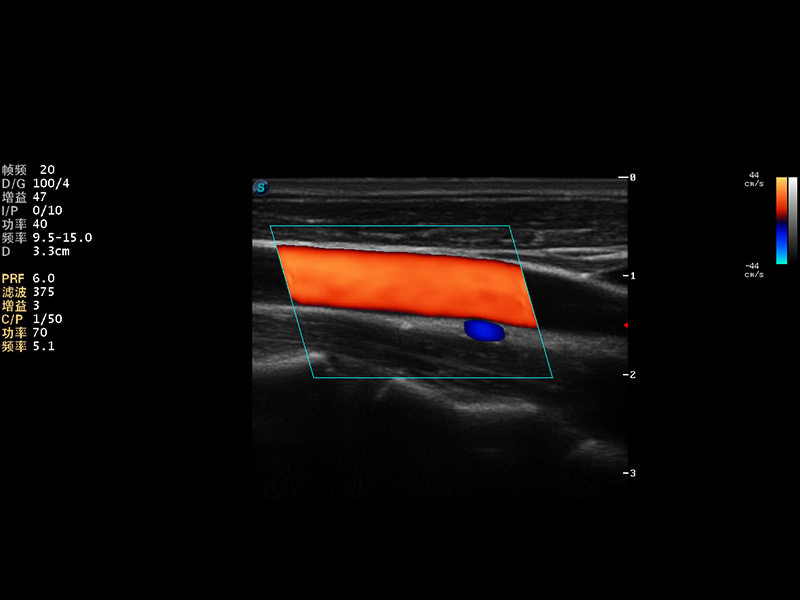

S9便携式彩色多普勒超声诊断仪是球速体育入口研发的高端便携彩超设备,外观设计新颖、产品性能卓越。S9在便携超声领域采用了突破传统的触摸屏交互设计,并以先进的软件硬件技术和设计理念,为您带来清晰的图像质量、稳定的工作性能和便捷的操作体验。

AutoC智能血流追踪